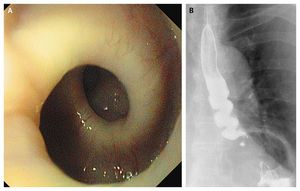

An 87-year-old woman with severe retrosternal pain and intermittent dysphagia was referred to the clinic for further evaluation. She described paroxysms of crampy pain almost exclusively during the intake of solid foods. In the past several months, she noted a weight loss of 5 kg. Endoscopy revealed a pronounced helical configuration of the esophageal lumen (Panel A and Video). Strong esophageal contractions occurred such that any advancement or withdrawal of the endoscope was hindered for several seconds. A barium swallow revealed a corkscrew appearance (Panel B). High-resolution manometry of the esophagus showed high-amplitude pressure waves, indicating a hypertensive peristaltic disorder of the esophagus. Because this patient had normal relaxation of the esophagogastric junction, no premature contractions, and a mean distal contractile integral (a calculation of the amplitude, duration, and span of the esophageal contraction) greater than 5000 mm Hg•sec•cm, this motility disorder can be described as nutcracker esophagus. After a trial of high-dose proton-pump inhibitors led to no clinical improvement, we initiated treatment with long-acting diltiazem, which had only a limited clinical benefit and had to be stopped because of severe ankle edema. Luc Biedermann, M.D. Oliver Götze, M.D. University Hospital Zurich, Zurich, Switzerland source: nejm.org